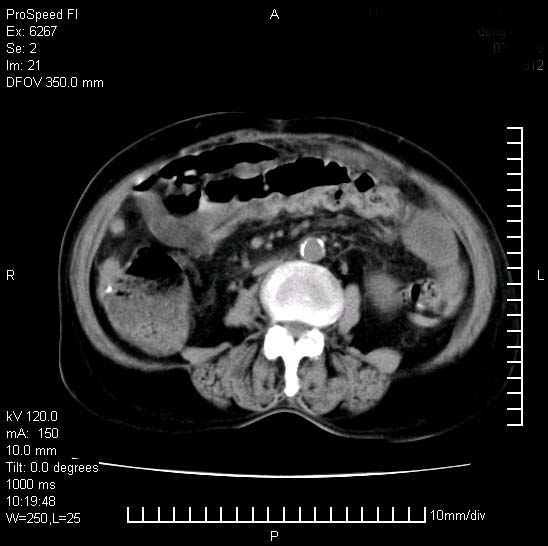

患者糖尿病,腹痛,恶心,呕吐。黄疸,意识较差,血糖很低(数值不详),临床以胆囊,胆管炎,低血糖反应收治。看的腹片少,各位帮忙看看,胰腺有问题吗??

1.胰腺体积增大,胰周脂肪间隙消失,胰腺炎可以确定。必要时实验室进一步检查。

2.胆囊炎,胆石症。

胰腺体积增大,胰周脂肪间隙消失,考虑胰腺炎。胆囊炎,胆石症。

脾大,原因?胆结石;胰腺肿大,边缘模糊,建议查定性指标血尿淀粉酶,除外胰腺炎

考虑胰腺炎。胆囊炎,胆石症。脾大。

1)考虑胰腺炎;建议查血尿淀粉酶。2)胆囊炎,胆囊结石。3)脾大。